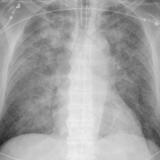

APE 3

Date: 11/05/2005

Views: 4001